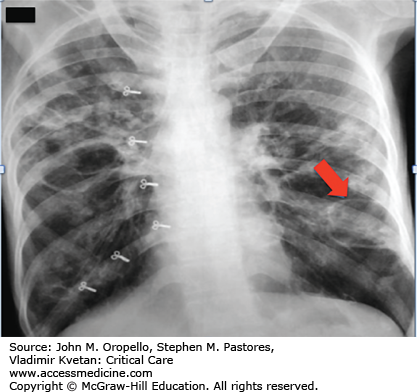

Pneumatocele in Staphylococcus pneumonia.